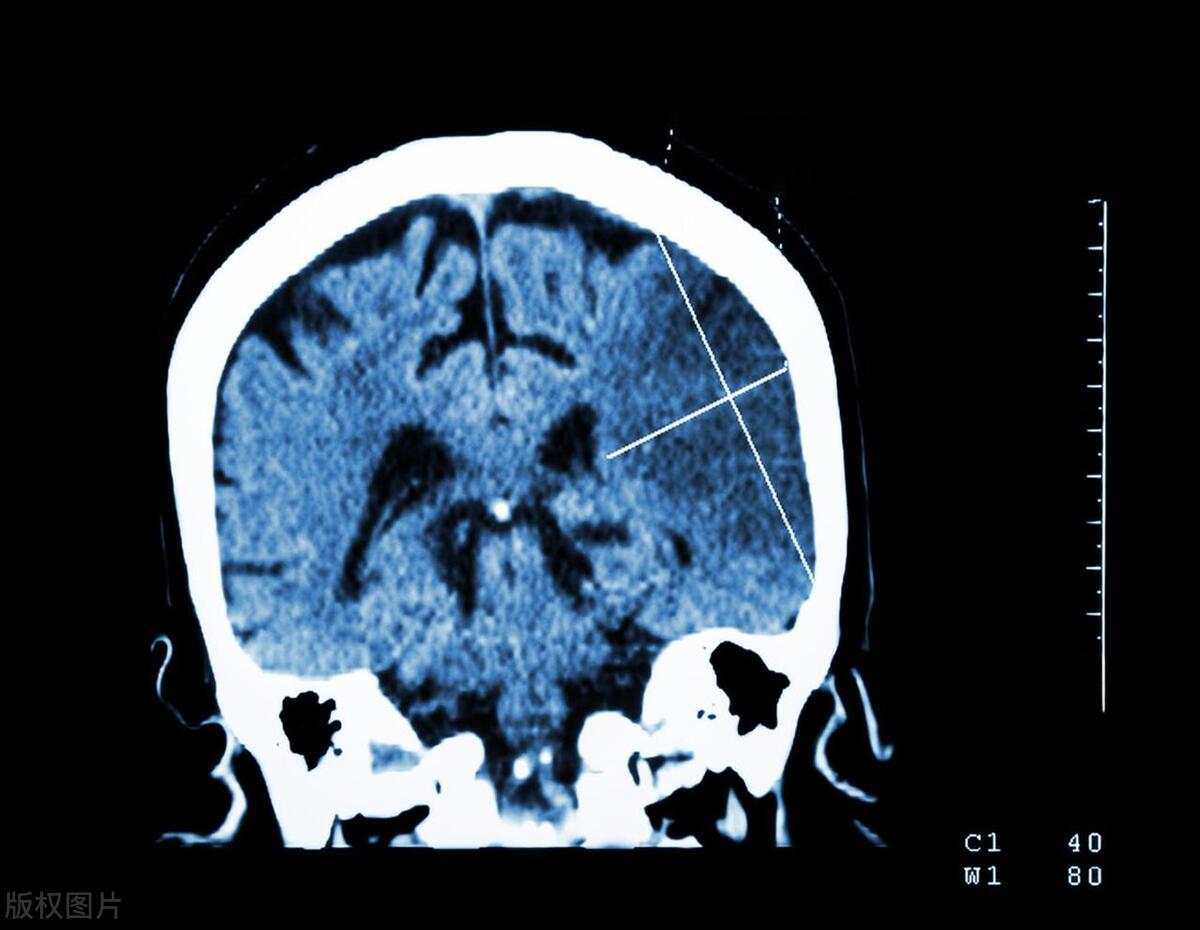

脑梗,这个现代医学名词,在中医理论中属于“中风”范畴。中医认为,脑梗的发生与人体内环境失衡、气血不畅密切相关。在中医辨证施治的理念下,脑梗的治疗不再是一刀切,而是因人而异、因症而异的个性化方案。